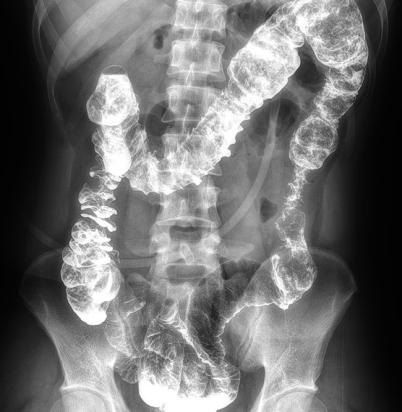

多功能動態(tài)平板DR,采用U型臂結(jié)構(gòu),具有靜態(tài)DR攝影、數(shù)字透視、數(shù)字造影和可視化攝影的功能。

電動旋轉(zhuǎn)內(nèi)平衡結(jié)構(gòu),可實(shí)現(xiàn)快捷擺位,滿足特殊體位的靜態(tài)與動態(tài)檢查。